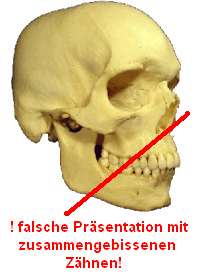

Die falsche

Die

immer völlig falsch mit zusammengepressten

Zähnen (hier ein Schema von wikipedia). Die

Ruheschwebelage scheint nicht bekannt [7].

Auch das

Schädelmodell des anatomischen Museums Basel

ist mit zusammengepressten Zähnen

dargestellt, anatomisch völlig falsch und

absolut schädlich für die Zähne. Die

Ruheschwebelage scheint nicht bekannt [7].